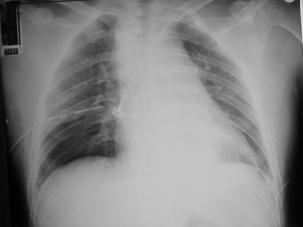

Pneumotorace sufocant bilateral Pneumotorace sufocant stang

Pneumotorace

sufocant stang Pneumotorace

sufocant drept Pneumotorace

sufocant drept